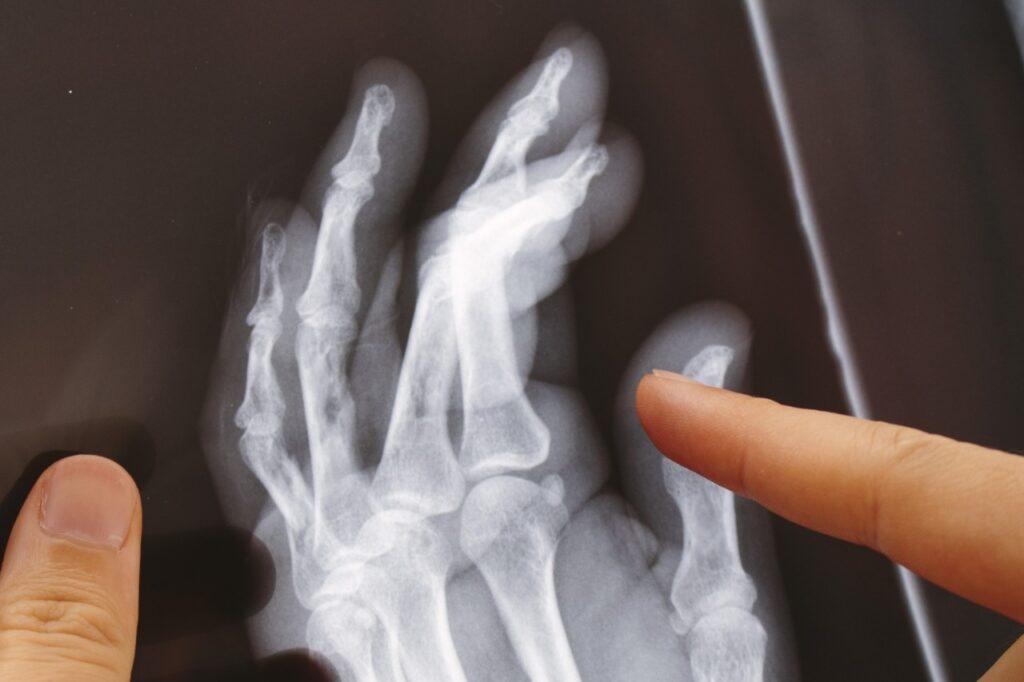

足の痛み

長時間の立ち仕事や歩行、過度な運動など、足に長時間の負荷がかかることで筋肉や組織へのストレスが増え、痛みを引き起こす原因となります。

また、合わない靴の選択や足の姿勢の問題が原因で、足のアーチの低下などを引き起こし、痛みを伴うことがあります。

また、外反母趾など変形に伴う病患も痛みの原因となります。

足の痛みで考えられる疾患

治療方法